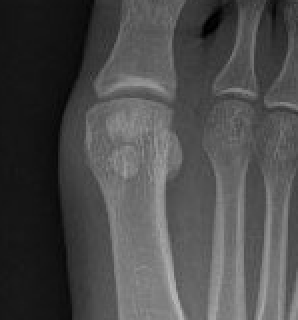

Bipartite sesamoid

Incidence

Tibial bipartite 10%

Bilateral 25%

Fibular bipartite rare

Bipartite sesamoids